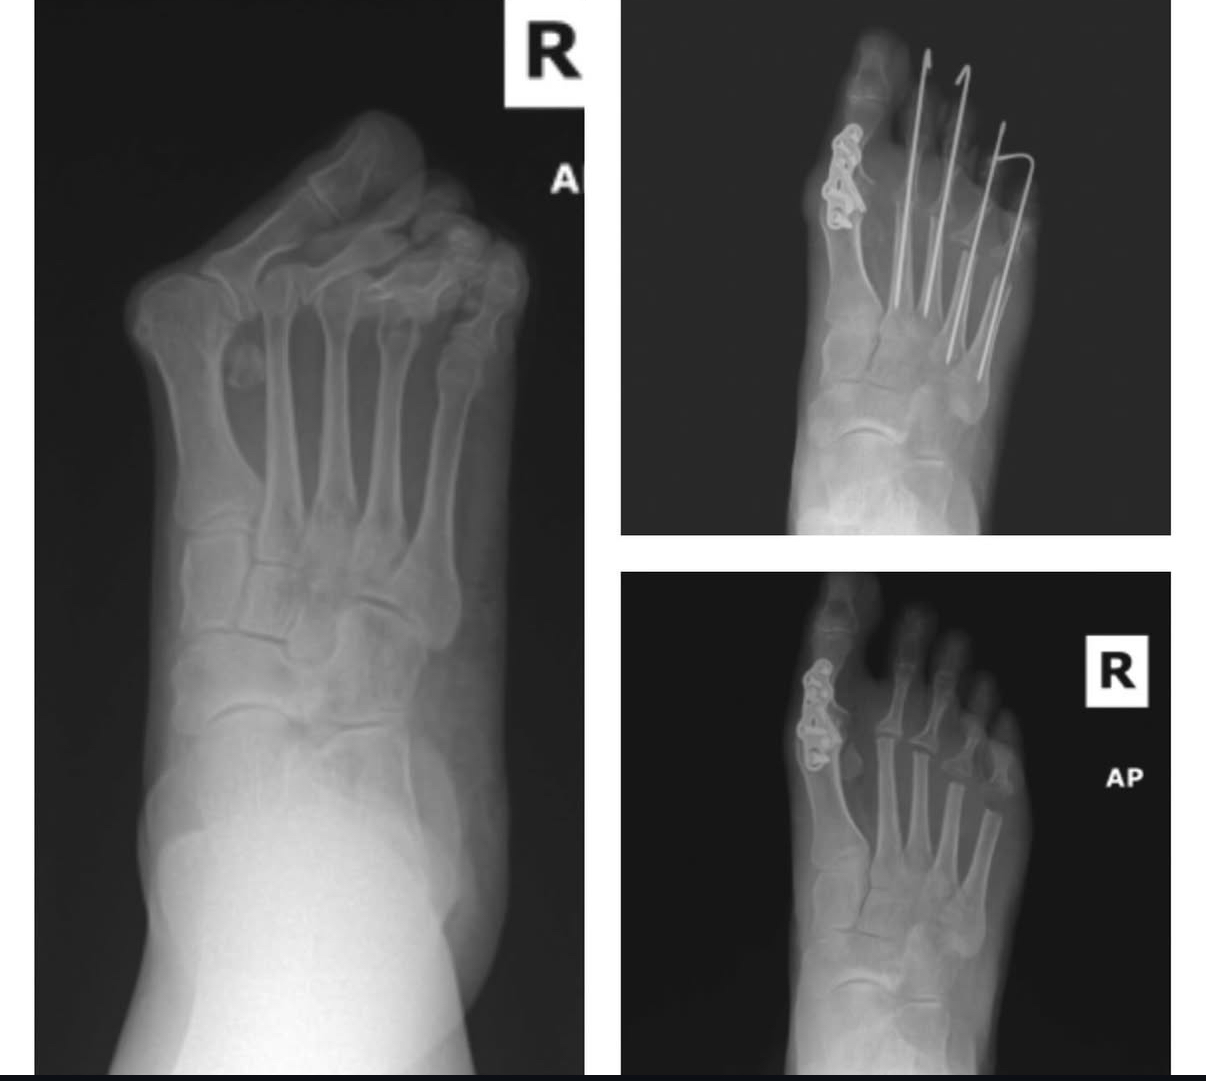

Rheumatoid foot

Pre and post XRS for severe rheumatoid foot pre and post XRS